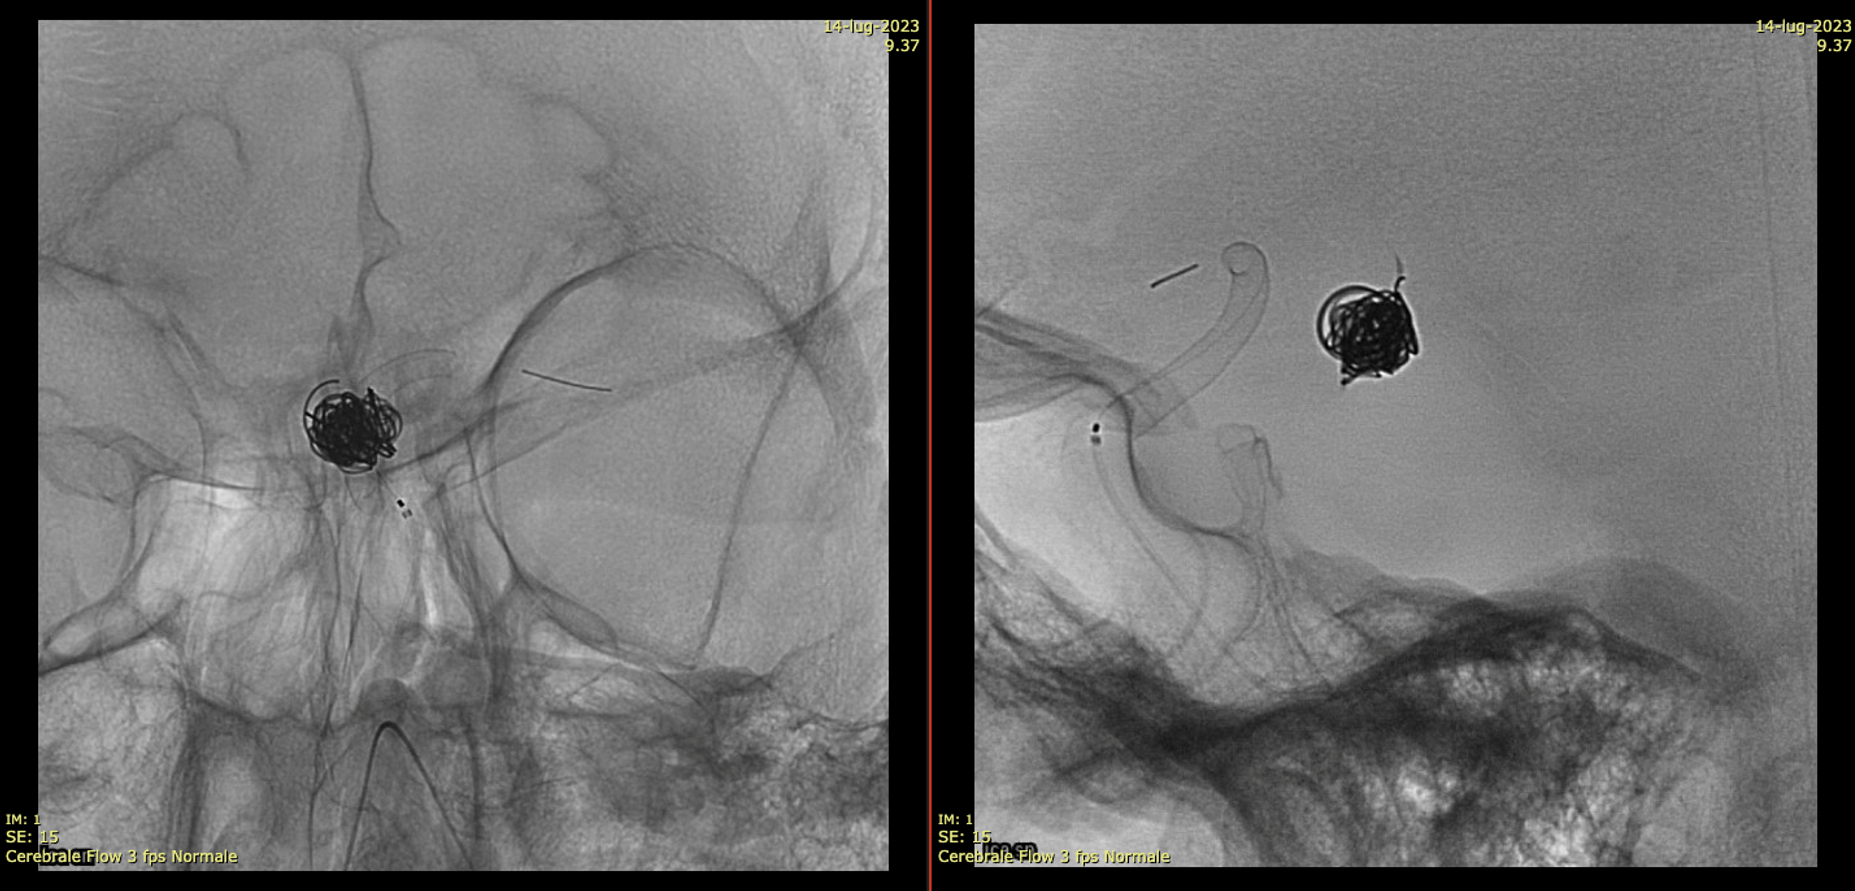

Very Important Case of Aggressive Basilar Bifurcation Aneurysm

Unruptured basilar tip aneurysm treated in 2010 with PED between right P1 and basilar.

The aneurysm was kept open by the left (contralateral) PCom — again, we know this much better now than in 2010. And its very important.

13 year later. The aneurysm was mostly thrombosed and was growing, becoming symptomatic. The good old analog Philips workhorse is gone… Welcome to the digital world or Azurion

Noncontrast / dry Vaso-CT, 22 cm FOV 20 seconds acquisition, followed by a secondary reconstruction with 50% FOV and 5123 resolution; Thick MIP.

Two Lvis EVO have been used (in inverse Y or ? lambda shape). The first from the left PCom into the left SCA. The second from the left PCom into the right SCA. Another microcatheter in jailed in the aneurysm for the subsequent coiling.

There are no labels or arrows on any of the devices. If you are not sure what is going on, we suggest studying the images until you do.

Thick MIP reconstruction of a Vaso-CT acquired with manual injection of right vert and left ICA at the same time. Vaso-CT, 22 cm FOV 20 seconds acquisition, followed by a secondary reconstruction with 67% FOV and 5123 resolution; Thick MIP.

The procedure finished with coiling of the basilar tip around the stents and PTA of right SCA stent at the crossing of the other stent

Post Rx. The key to this procedure, other than sophisticated understanding of the problem and the materials to be used, is a consistently effective antiplatelet state. Doing this without IIbIIIa in the lab for example risks major disaster.

At the 8 months follow-up, after passing from DAPT to SAPT, the aneurysm became smaller, with corresponding clinical improvement.

This is a key point — the success of treatment in aneurysms of this type is judged by cross-sectional imaging, not angio. With aneurysm shrinkage a good angiogram is guaranteed, while there are many examples of good-looking angiograms with moribund patients.